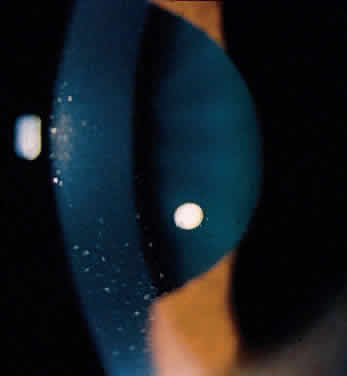

Acute iridocyclitis may be caused by herpes simplex (Fig. 12), herpes zoster, and other suspected viral disorders. The accompanying skin manifestations and associated corneal lesions are helpful in establishing the diagnosis. These should be considered when the acute symptoms of redness, pain, photophobia, and tearing are found with poorly defined keratic precipitates, cells in the anterior chamber, sector iris atrophy (Fig. 13), and other acute anterior segment inflammatory changes, especially if unilateral.

Fig. 12. Acute herpes simplex iridocyclitis and subsequent keratitis.

Fig. 13. Corneal endothelial cells, indistinct keratic precipitates, and sector iris ischemia and atrophy (2 to 3 o'clock) with herpes simplex iridocyclitis.